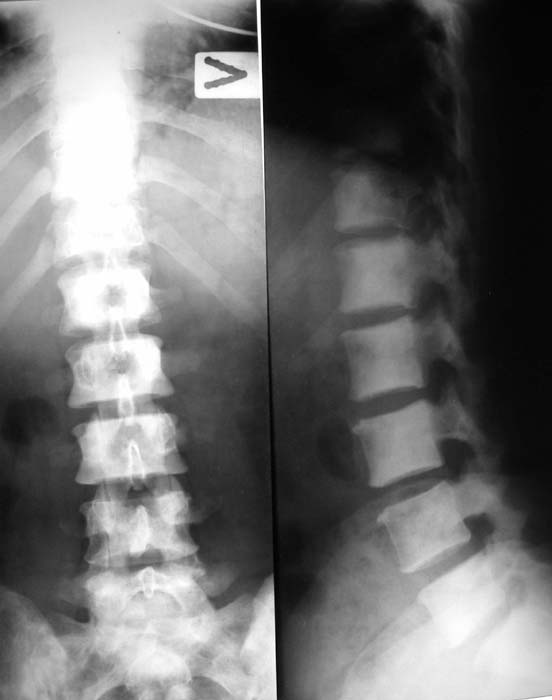

При МРТ (29.10.06) обнаружены диффузно-очаговые изменения в пояснично-крестцовом отделе позвоночника предположительно вторичного характера.

В октябре 2006 г. по поводу маточного кровотечения (менопауза 4 мес.) выполнено УЗИ - гиперплазия эндометрия, полипоз. Операция - удаление полипа, выскабливание полости матки. Цитологический анализ - пласты переходного климактерического эндометрия.Проведено комплексное исследование. В приложении: рентгенограммы и томограммы поясничного отдела позвоночника; радиологические исследованиямолочной железы, ЖКТ, почек, грудной клетки, анализы.УЗИ (18.12.06.) щитовидной железы, молочных желез - без патологии (умеренный фиброз по ходу млечных протоков).

Остеосцинтиграфия 4.12.06. - активный остеобластический процесс в поясничном, нижнегрудном отделах позвоночника, костях таза.Местными онкологами онко-процесс исключен. Фтизиатрический и онкогематологический диагнозы исключены.